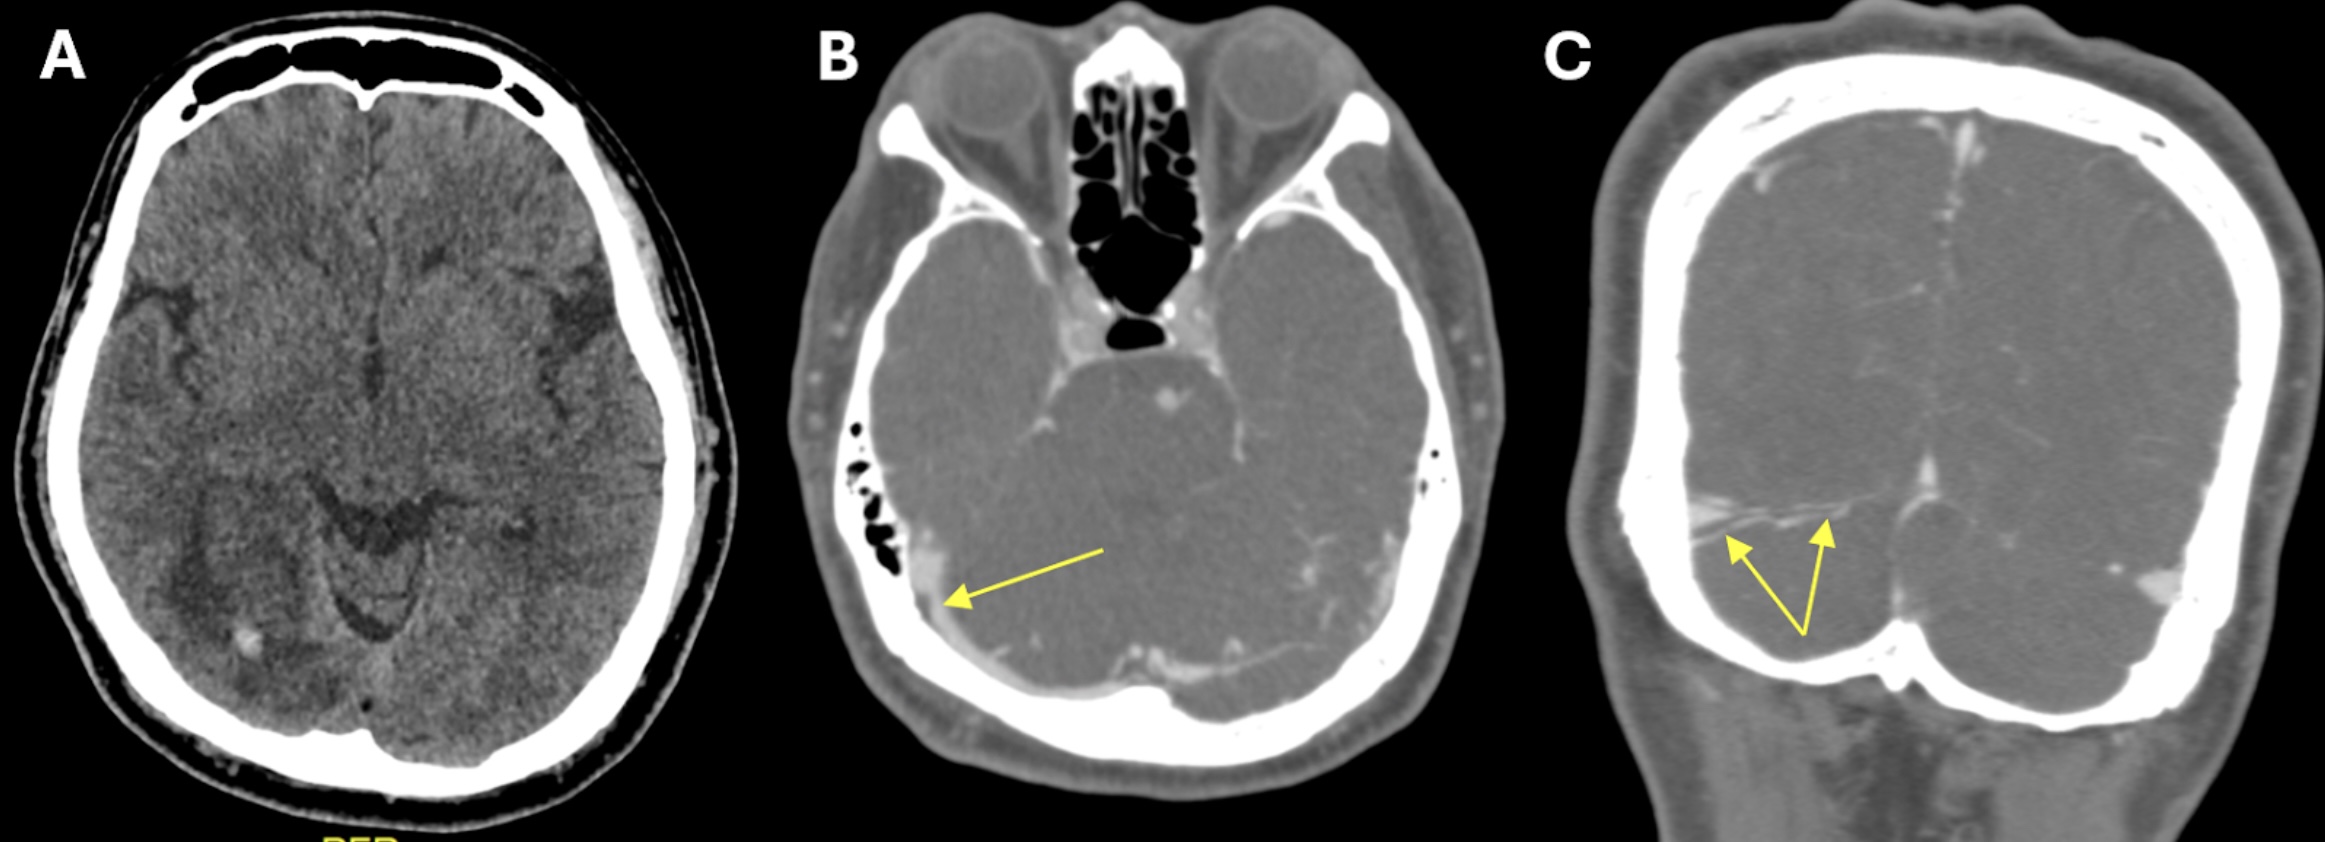

FIGURE 1: (A) Non-contrast CT brain demonstrated acute focal hemorrhage at the right occipital lobe withperihemorrhagic hypodensity extending to the right parieto-occipital region; (B) Subsequent CT venography in axial plane revealed thin linear isodensity within the right transverse sinus; (C) CT venography in coronal plane confirmed the filling defect within the right transverse sinus, consistent with thrombus